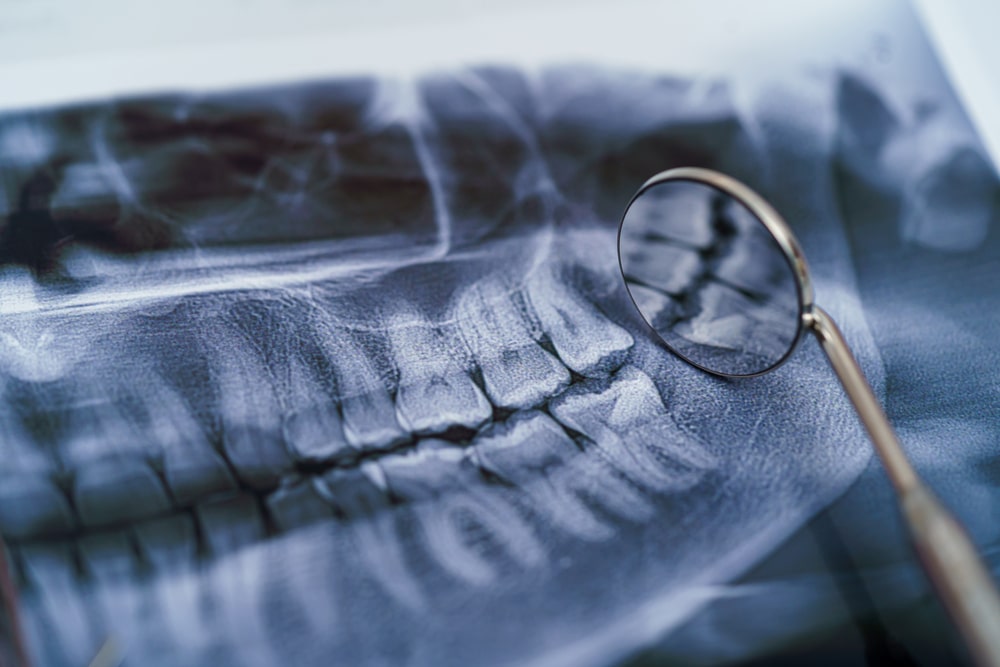

Endodontics is a specialized field of dentistry that focuses on treating issues within the tooth’s pulp and roots. When the inner part of a tooth becomes inflamed or infected, endodontic procedures can help prevent the need for an extraction. These treatments allow patients to keep their natural teeth while eliminating discomfort and improving oral health.

A root canal removes infected pulp, cleans the inner canals, and seals the tooth to prevent reinfection. This procedure allows patients to keep their natural teeth while eliminating the source of discomfort. Many people feel relief shortly after treatment and can return to normal activities the next day.

If a previous root canal does not heal properly or becomes reinfected, retreatment may be needed. The procedure involves reopening the tooth, removing old filling material, disinfecting the canals, and resealing the tooth to prevent future infection.